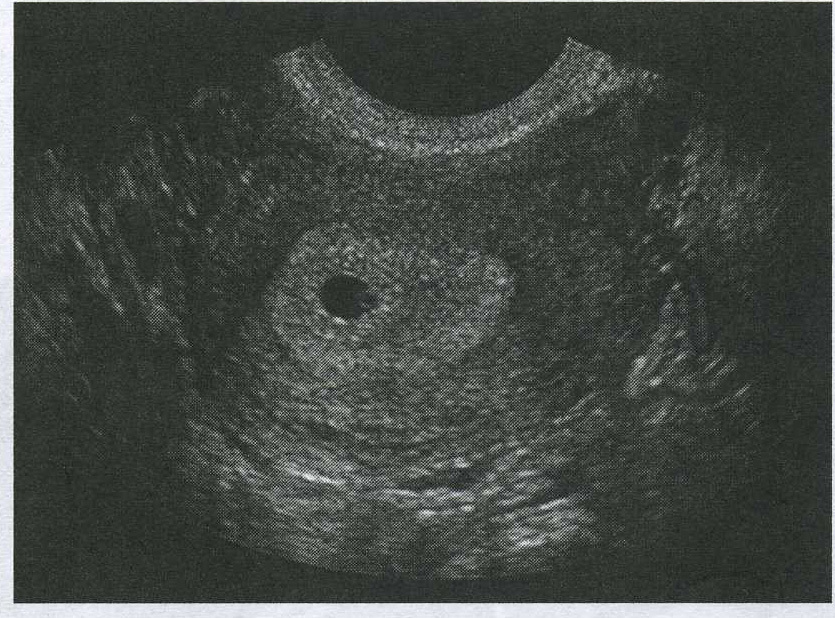

identify the findings in this early pregnancy

thickend dicidua, gestational sac and secondary yolk sac

intrauterine gestation